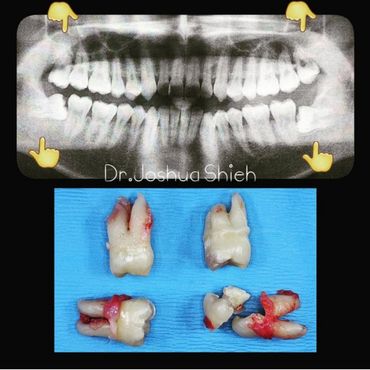

If the tooth is planned for extraction, an x-ray of the area will be taken to plan for the type of extraction.

Wisdom teeth are the third set of human molars. Unfortunately, in some cases, those teeth are impacted fully or partially in bone or soft tissue and cannot erupt causing pain, discomfort and swelling. Additionally, most people have difficulty accessing these teeth during brushing or flossing causing accelerated decay and gum problems. Wisdom teeth have also been notorious for causing crowding, improper bites and pressure when they start erupting. The arrival of these late-breaking teeth can cause trouble as they are often impacted (trapped in the jawbone) because there is not enough room for them in the mouth. Our jaws are a lot smaller than those of our early human ancestors, who needed bigger jaws and more teeth for the type of food they chewed. In most people, wisdom teeth can do more harm than good and we often recommend their removal.

It can take a long time for wisdom teeth to erupt and you may not even notice the harmful effects in your mouth until you experience sudden and severe discomfort. Cramped for room, impacted wisdom teeth grow out at odd angles or remain trapped below the gums. Adjacent teeth can become prone to decay because of the unfavourable position of the wisdom teeth.